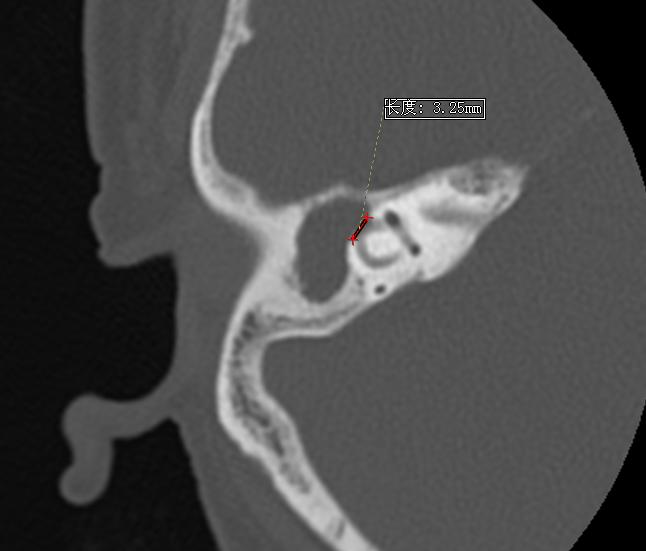

据了解,较小的胆脂瘤切除手术可以在内窥镜下施行,但王阿姨的胆脂瘤侵犯范围较大,需要在显微镜下进行。在耳鼻咽喉-头颈外科黄志纯主任的指导下,丁小琼博士为王阿姨在显微镜下施行手术。丁小琼博士首先在王阿姨耳后切开一个小口,随后切除胆脂瘤。胆脂瘤切除后,发现耳内的外半规管被胆脂瘤挤压,外半规管外侧骨头破坏较为严重,形成约3毫米长的瘘口,而这就是导致眩晕的罪魁祸首。紧接着,丁小琼博士用筋膜以及骨粉对瘘口进行修补,术中同时发现患者的面神经骨管也被胆脂瘤破坏,面神经约有5mm长暴露,如果胆脂瘤再长大一点,便会导致面瘫。丁博士赶紧又用筋膜覆盖住面神经。手术很成功,历时三小时。术后6天王阿姨出院时,已不再头晕,活动自如。